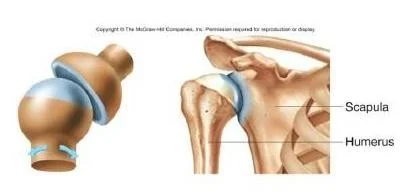

Ball & Socket(hip)

- Scapula

- Humerus